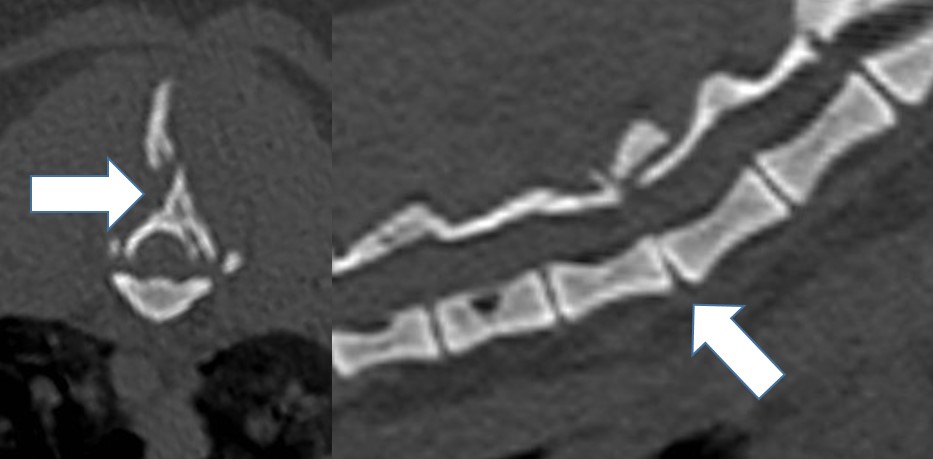

At our hospital we see cat patients after sustaining a trauma. They can have spinal fractures (Fig 1). But because cats have normally a very elastic body, they bend the spine during the trauma until the disk ruptures with a traumatic disk extrusion as consequence. The damage to the spinal cord can be severe, but in most cases a surgery would not help. The MRI is the only diagnostic tool to clearly diagnose such a traumatic extrusion (Fig 2). Fractures to the sacrum and the first vertebra of the tail are also typical for cats. The nerves to the bladder are often damaged in these patients, so the cat has to be in the hospital to ensure the treatment of bladder and fracture (Fig 3).

Middle aged and older cats sometimes change their behavior, they don’t jump up anymore, play less and maybe do not move so much outside. This is often a sign of pain in the hind legs or in the spine. Like German Shepherd Dogs cats can have degenerative lumbo-sacral disease (Fig 4). The life quality of these cat patients can greatly improve with the right pain medication, but the disease should be diagnosed first with a CT examination, because the pain could also come from another place, for example a cruciate ligament rupture. Surgical treatment of lumbo-sacral disease is rarely necessary in cats.

Fig 3: Tail fracture in a cat Fig 4: Lumbo-sacral disease